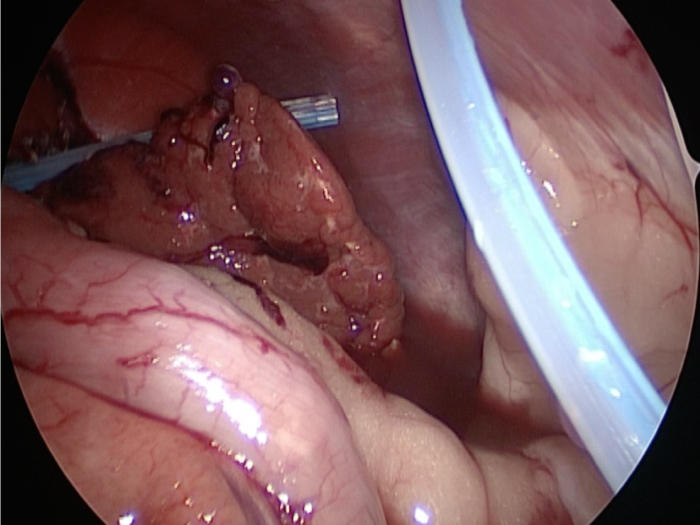

胆嚢が破裂した様子を腹腔内にカメラを入れて観察した像です。

胆嚢から漏れ出た胆汁が腹腔内に確認できます

他院より紹介。胆嚢炎がひどく繰り返す嘔吐がありました。 腹膜と一部横隔膜に胆嚢ががっちりと癒着していました。 体重が2kgと体も小さかったのですが、飼い主さんの希望もあり、腹腔鏡下で手術を実施することになりました。

丁寧に丁寧に出血をコントロールしながら少しずつ手術をすすめていきます。

癒着(矢印)がひどく胆嚢を確認することができませんでした。

このように癒着しているときはギリギリで剥がすとひどく出血をおこすことがあるので無理にはがそうとしないで、脂肪の血管に注意しながら脂肪ごと剥がしていきます。